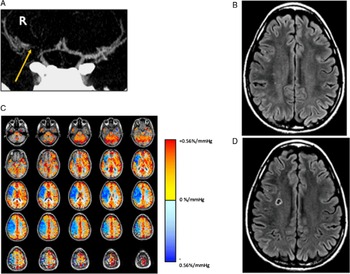

The incidence of stroke in the cohort at 1 year was 4.8 % (4/83). All the strokes occurred in patients with impaired CVR (4/69) and none in patients with normal CVR despite no revascularization (Figure 4). However, it was not statistically significant (4/69 vs 0/14 p = 1.0, Fisher’s exact test)). Among the patients with impaired CVR, all the strokes happened on the nonrevascularized side; two strokes occurred in patients who had no revascularization and the other two occurred in the contralateral nonrevascularized side in patients with bilateral SOD who had ipsilateral revascularization. (4/16 vs 0/53 p = 0.05, Fisher’s exact test). Note that all the strokes occurred in the area, which showed impaired CVR (Figure 4). Six (6/69, 8.7%) patients with impaired CVR and no revascularization had self-reported worsening of cognitive function at 1 year. Among the patients who had normal CVR, three patients (3/14, 21%) had episodes of TIA’s (ipsilateral to SOD) and one patient (1/14, 7.1%) complained of worsening cognitive function at 1 year. There were no clinical strokes in this group.

Figure 4: Example of a patient who presented with transient left face and upper and lower extremity paresthesia and weakness. (A) CT angiogram shows severe narrowing of the right middle cerebral artery (yellow arrow). (B) T2-weighted FLAIR image showed no evidence of brain infarct. (C) CVR study shows reduced (paradoxical) reactivity throughout the right MCA territory and preserved reactivity elsewhere. (D) 4-month follow-up MRI demonstrating a new infarct in the right MCA territory corresponding to the region of impaired CVR.